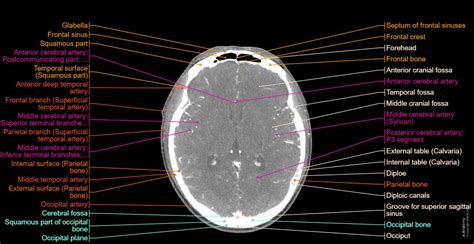

• Advanced imaging and diagnostic services: St Joseph Hospital Chicago's advanced imaging and diagnostic services, including MRI and CT scans, enable accurate diagnosis and treatment of various medical conditions.